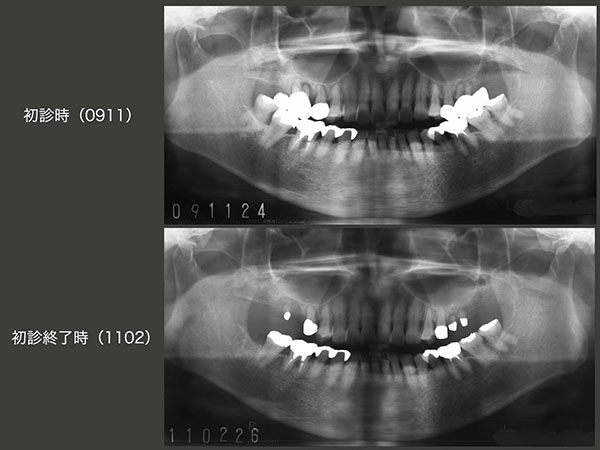

初診時と初診終了時のパノラマX線写真の比較.初診時右上6は3根あるが,左上6は以前に口蓋根を抜歯しており2根しかない.想像するに歯根の数の多い右側で主に咀嚼していたが,歯根破折が生じ咬めなくなったので左側咬みになったが,こちらも頰側根の分岐部に歯根破折が生じてしまい,結局両方の奥歯で嚙めなくなり,当院を受診したのではないかと思われる.